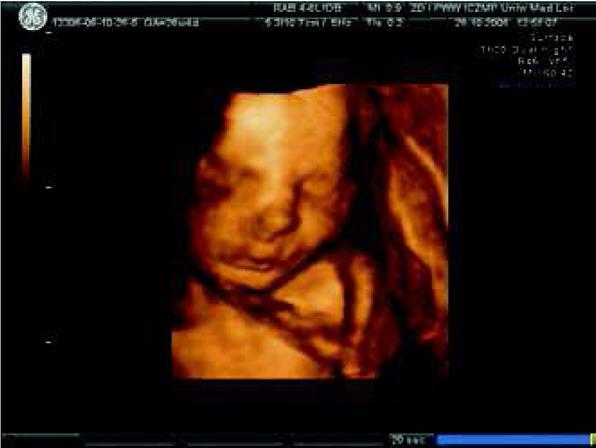

Fig. 2